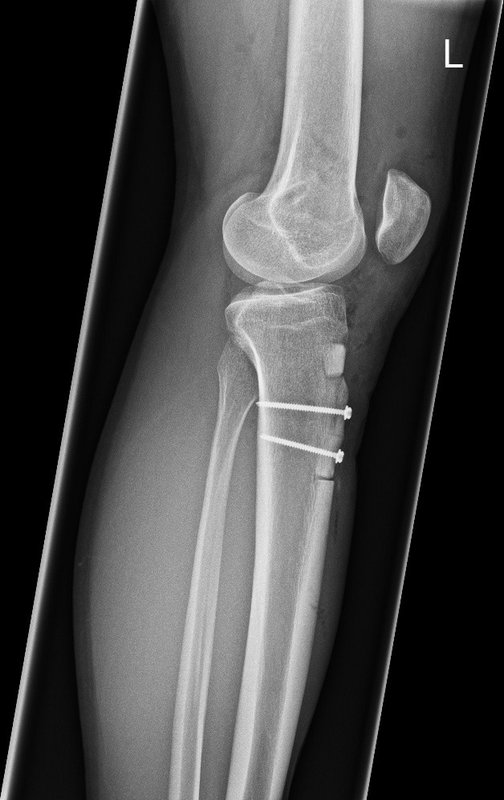

Tibiakopf Fraktur

Die arthroskopisch assistierte Frakturversorgung (insbesondere am Tibiakopf) im Rahmen von Band- bzw. Kombinationsverletzungen ist ebenfalls ein Schwerpunkt der Abteilung. Der ärztliche Direktor PD Dr. med. Schlumberger ist im DKG-Komitee „Frakturen“ vertreten.